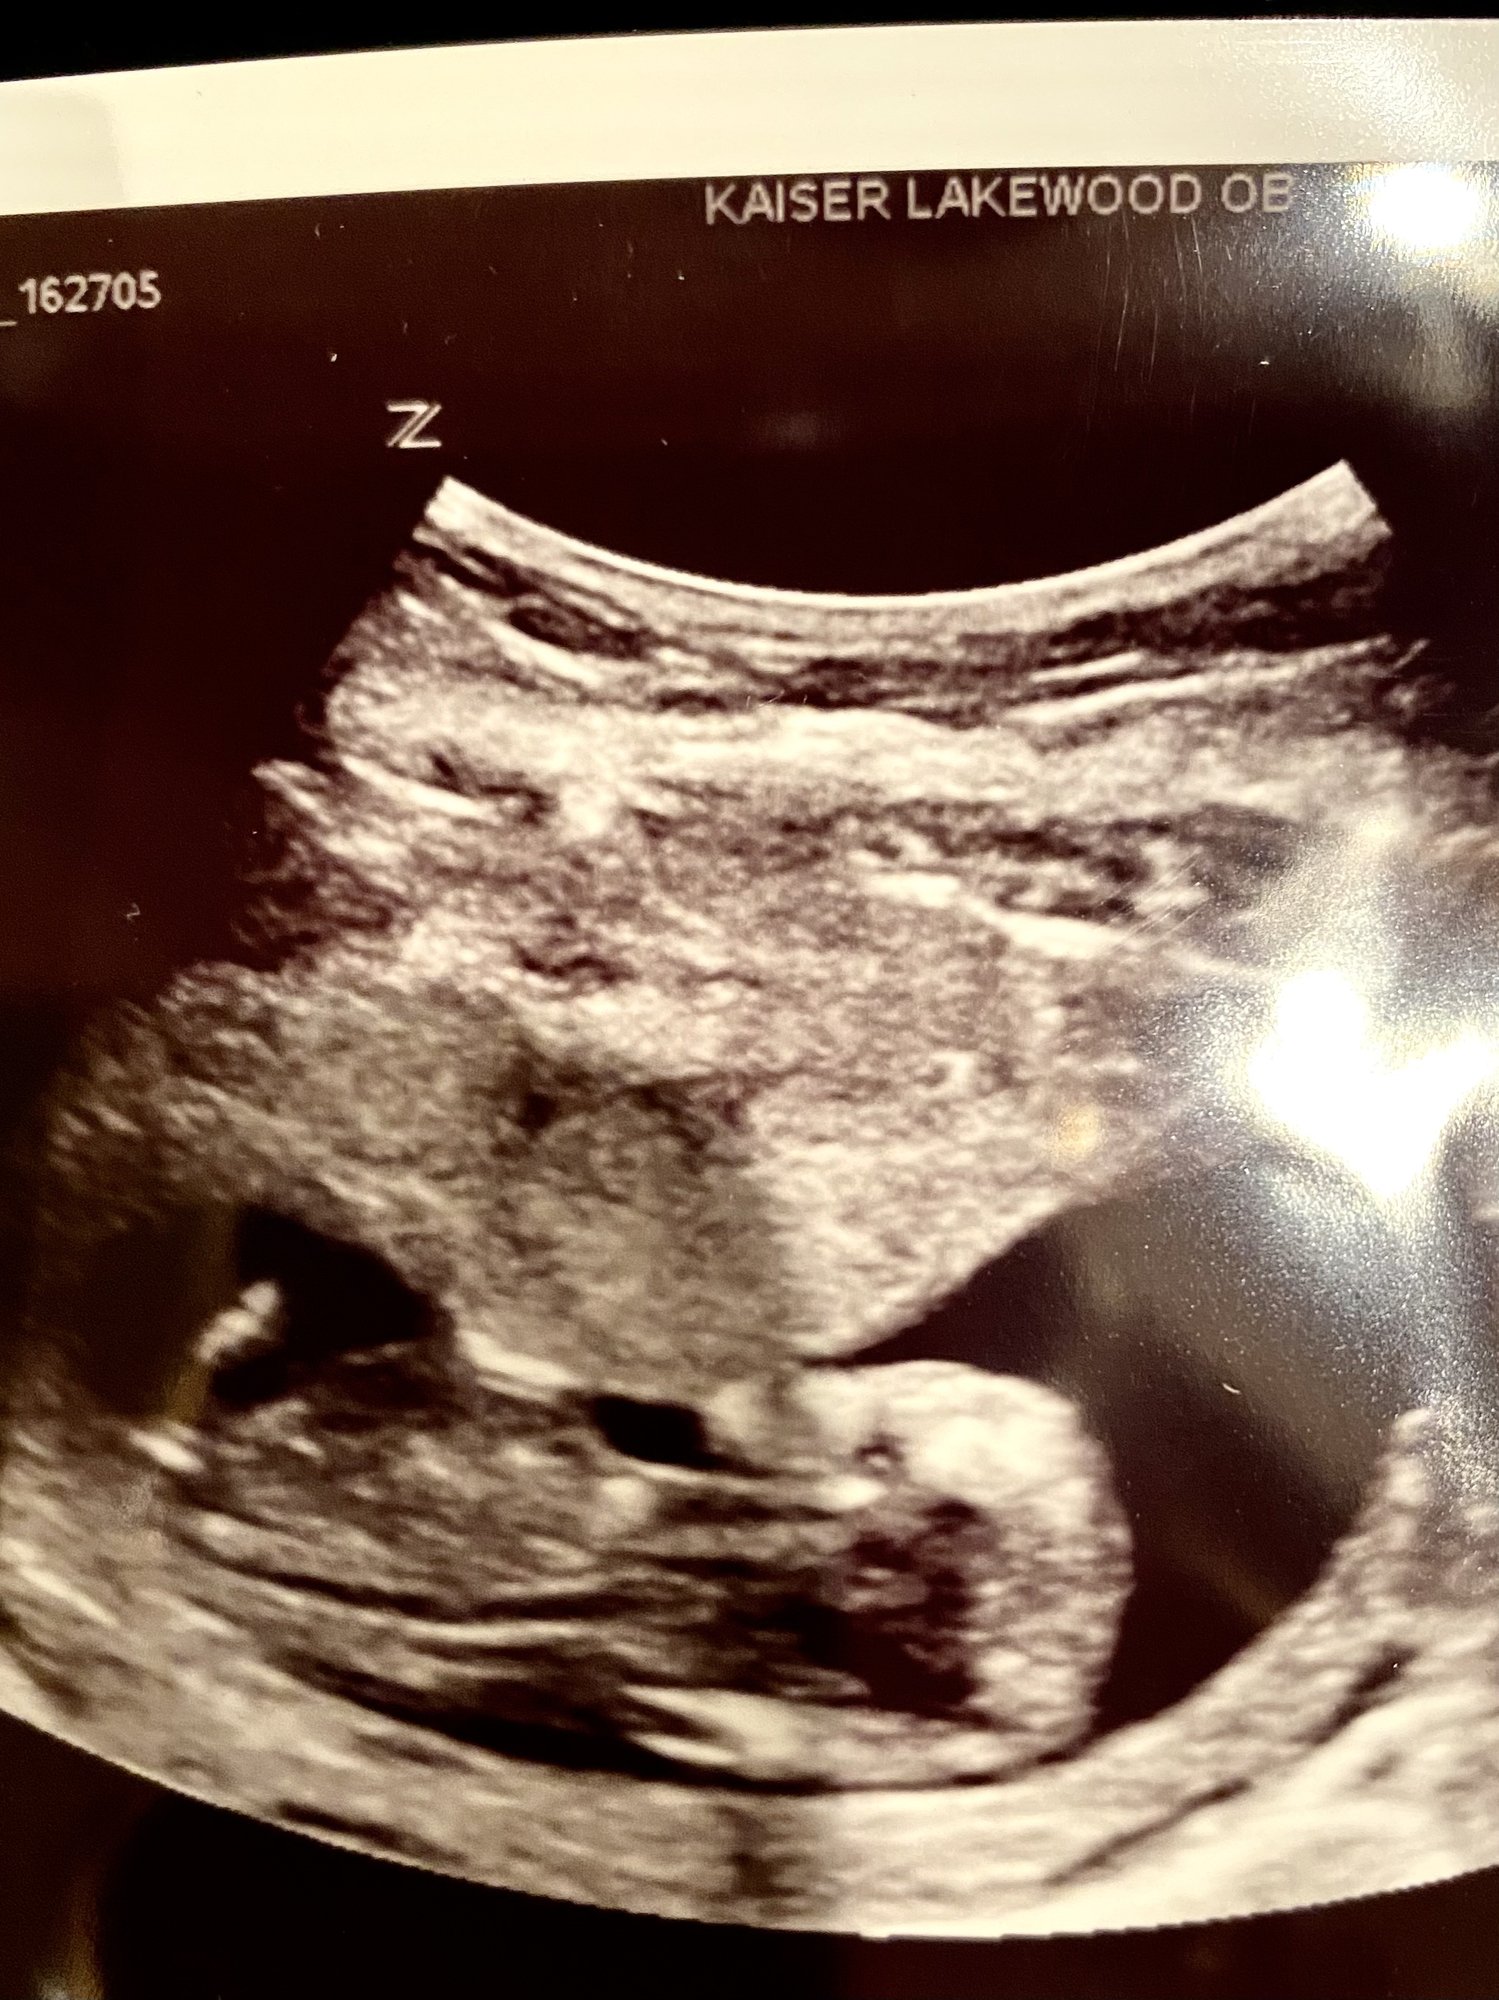

I am new TB! We are 15 weeks today! This US was taken on the 16th & the GA is incorrect on the US, the paper work i got after the doctor saw it, shows that i was further along then i thought! We have a due date of Jan 14th! We announced last week on facebook, I wanted to wait till we were clear out of the first trimester. I did the blood work, still waiting on the gender!

7/26/21 Ultrasound at 13 weeks 5 days. They say everything looks good. Baby has all it's limbs and organs.

Super excited to find out the sex so I can start buying things and nervous for the NIPT results, but I'm always nervous about testing sooo......